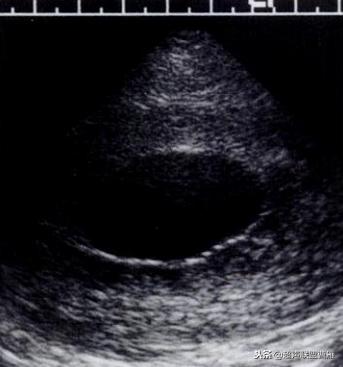

妊娠37天超声检查卵黄囊可以显示,羊膜腔及胚胎不能显示

妊娠37天出现卵黄囊

在妊娠妊娠38天前后(36-40)天可以见到卵黄囊。 孕囊在6-9mm的可以见到其中有卵黄囊。